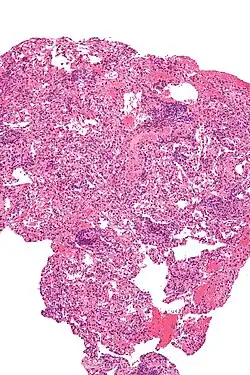

Micrograph showing lung transplant rejection. Lung biopsy. H&E stain.

As with any surgical procedure, there are risks of bleeding and infection. The newly transplanted lung itself may fail to properly heal and function. Ten percent of transplanted lungs have a partial tearing (dehisence) of the surgical airway connection.[2] Because a large portion of the patient's body has been exposed to the outside air, sepsis is a possibility, so antibiotics are given preventatively. Other complications include Post-transplant lymphoproliferative disorder, a form of lymphoma due to the immune suppressants, and gastrointestinal inflammation and ulceration of the stomach and esophagus.

Transplant rejection is a serious concern, both immediately after the surgery and continuing throughout the patient's life. Because the transplanted lung or lungs come from another person, the recipient's immune system will see it as an invader and attempt to neutralize it.[2]